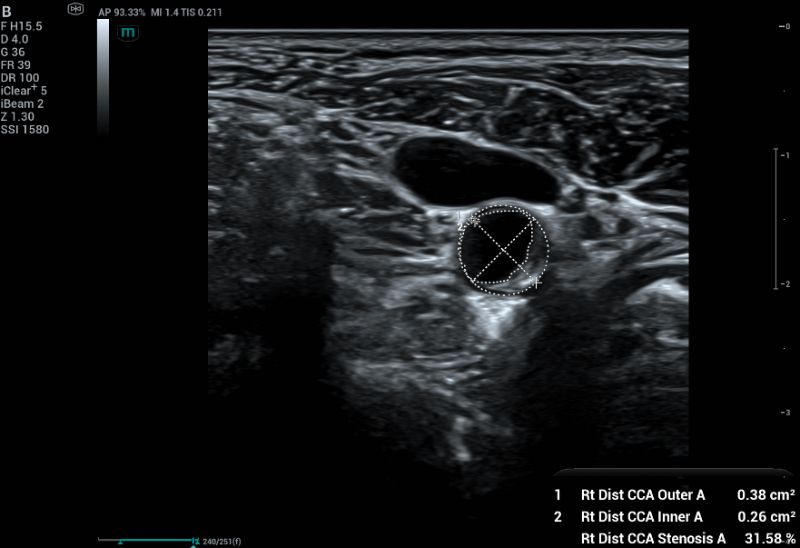

To measure percentage of stenosis, diameter-based measurement (Fig 3) remains the most widely accepted method to quantify carotid stenosis. However, for plaques that are non-circular or crescent-shaped in cross-section, a single diameter measurement can significantly underestimate the true severity of the narrowing.

Area-based measurement using cross-sectional imaging (Fig 4), the area of the residual lumen can be directly measured. This method can more accurately quantify stenosis in plaques that are irregularly shaped and asymmetric in cross-sectional images. However, the non-linear relationship between diameter and area (A=πr2) means that the area method can yield higher percentages of stenosis than the diameter method.

Measuring percentage of stenosis using diameter-based method.  This method measures the full vessel lumen and patented lumen.

Fig.3: Measuring percentage of stenosis using diameter-based method. This method measures the full vessel lumen and patented lumen.

Measuring percentage of stenosis using area-based method. This method manually trace the full vessel lumen and patented lumen in axial plane.

Fig.4: Measuring percentage of stenosis using area-based method. This method manually trace the full vessel lumen and patented lumen in axial plane.

Relying on a single view can lead to inaccuracies. Using both longitudinal and axial views provides a more complete picture of the plaque and the vessel, ensuring a more accurate measurement of stenosis.